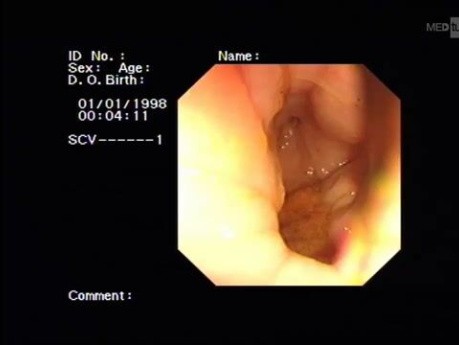

Vue Critique de Sécurité de la Cholécystectomie...

Afin d'éviter les lésions vasculobiliaires, la technique de vue critique de sécurité (VCS) est fortement recommandée lors de la dissection du triangle hépatocystique. Elle comprend les trois étapes suivantes...